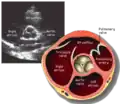

This view is obtained in the same window as the parasternal long, but with the probe rotated 90°. In this view, the aortic valve is seen in cross-section with the right ventricular inflow & outflow tracts visible with the tricuspid valve as well. Pulmonary valve is not visible in this view. Both the right and left atria are visible.

- Aortic valve in short-axis

- Aortic valve dysfunction, aortic sclerosis/stenosis